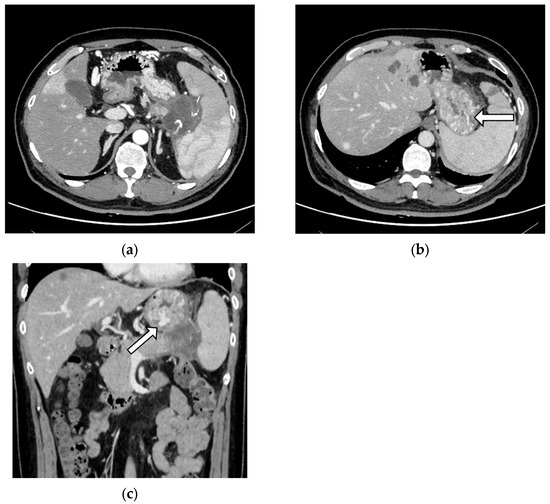

Emergency EGD was performed for suspected upper gastrointestinal bleeding in seven patients, of which sources of bleeding were identified in six (85.7%) and three (42.9%) showed signs of GV (one patient each had F1, F2, and F3 varices, respectively). Variceal rupture was only observed in one case belonging to the SHI group (p = 0.432) (Figure 2). All three cases of splenic artery pseudoaneurysm rupture, of which one was fatal, also belonged to the SHI group (p = 0.078).

Figure 2. A case of gastric variceal rupture. A 39-year-old man with known liver, lung, and bone metastases of pancreatic tail cancer presented with hematemesis. The most recent computed tomography revealed (a) splenic hilar involvement and multiple dilated vessels reaching the surface of the gastric mucosa (arrows) on (b) axial and (c) coronal images. The patient was successfully treated with endoscopic injection sclerotherapy followed by partial splenic embolectomy at a tertiary referral center.